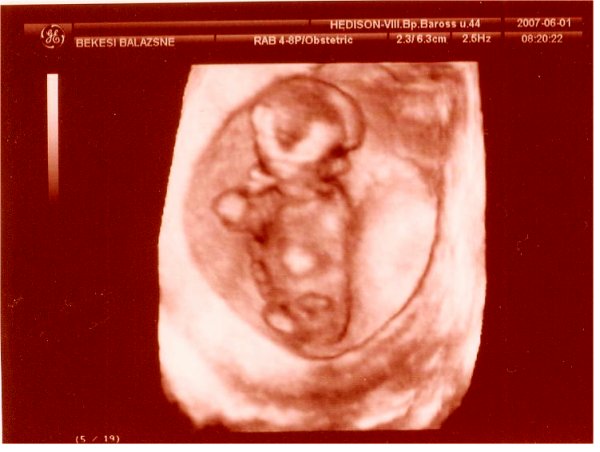

UH: befeküdt a drágánk fejfekvésbe. Ez nem is lett volna gond, ha nem a hátát és a popsiját mutatja egész uh alatt......... A kis arcocskáját befelé fordította, nem is láttuk! A doktornő is megszenvedett vele, pl. a szivecskéjét nem is tudta alaposan megnézni. Mondta neki, hogy forduljon meg, de nem hallgatott rá. Bízunk benne, hogy a jövő hét csütörtöki 4d-re megfordul, mert ha nem, hát nem sok esélyünk lesz bármire is. VAgyis semmi értelme nem lesz az uh-nak. Addig meg kell fordítanunk. Valahogy

Nemét nem akarta az orvos megmondani, mert nem nagyon volt benne biztos. Azt mondja, ha majd biztosabb lesz. Erre én rákérdeztem, hogy kisfiú? Ő visszakérdezett, hogy honnan gondolom? Mondtam, hogy megérzés. Erre ő: ő is úgy érzi. Nehéz volt megállapítani, hogy fiúcska, mert a lába közt sok volt a köldökzsinór. Megnézte áramlásmérővel, ahol volt áramlás, az a köldökzsinór volt, ahol meg nem, a kis kukija.

Itt van Ő: